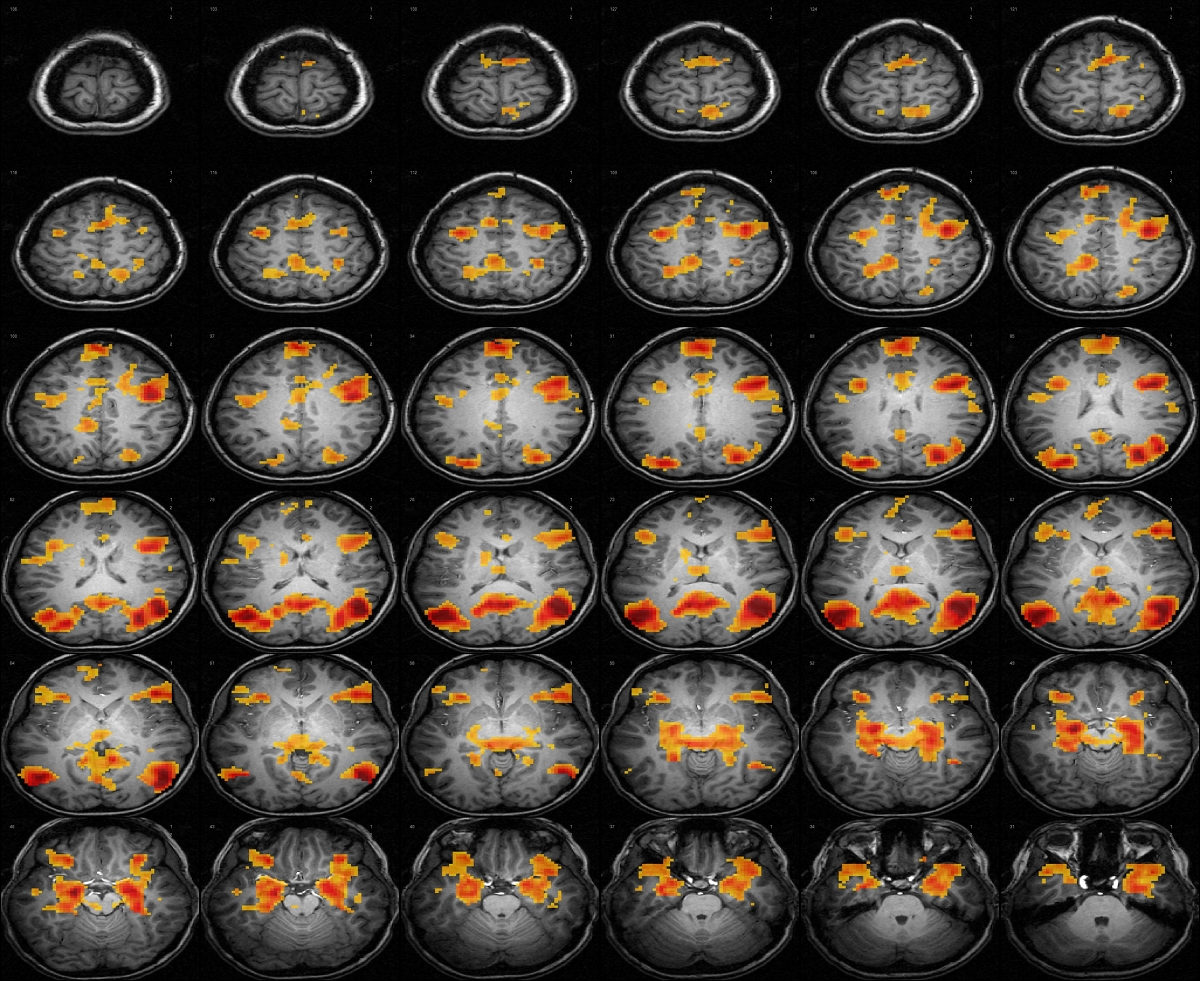

functional MRI, imaging-based diagnosis and prognosis

Areas of research:functional MRI, imaging-based diagnosis and prognosis